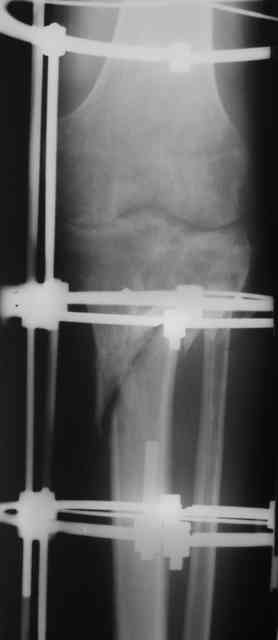

Р-граммы и фото за 4.05.2007 - 7-е сутки после операции.

Ход операции - линейным разрезом по передней поверхности голени обнажена зона ложного сустава большеберцовой кости. От кости отсепарованы медиально м/ткани. Из зоны ложного сустава убраны рубцовые ткани, мобилизован дистальный отломок. По передней поверхности удалены два осколка, связанных грануляциями. Произведено удаление грануляционной ткани из проксимального отломка (на вид сине-серого цвета), "чистого" гноя не было. Затем произведено наложение аппарата и репозиция отломков. По передне-медиальной поверхности образовался дефект до 4х2х2 см + полость в проксимальном отломке. Удаленные осколки очищены от грануляций, уложены в место дефекта, зажаты между отломками. После иссечения раны по передней поверхности, находящейся рядом с операционной раной, последняя ушита с большим натяжением.

Перелом мыщелка сросся. Проксимальный отломок очень порозный.

На перевязках - из раны небольшое кол-во сукровичного отделяемого. Отек голени умеренный, состояние кожи на фото.